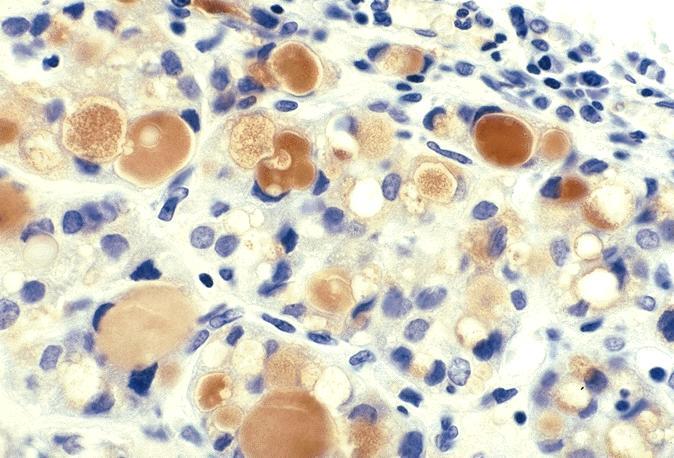

- Variants

- Signet ring cell follicular adenoma: signet ring cell change

- Clear cell follicular adenoma: follicular adenoma with clear cell change

Microscopic (histologic) images

Contributed by Shipra Agarwal, M.D., Andrey Bychkov, M.D., Ph.D., Mark R. Wick, M.D., Asmaa Gaber Abdou, M.D. and AFIP

Atypical adenomas: